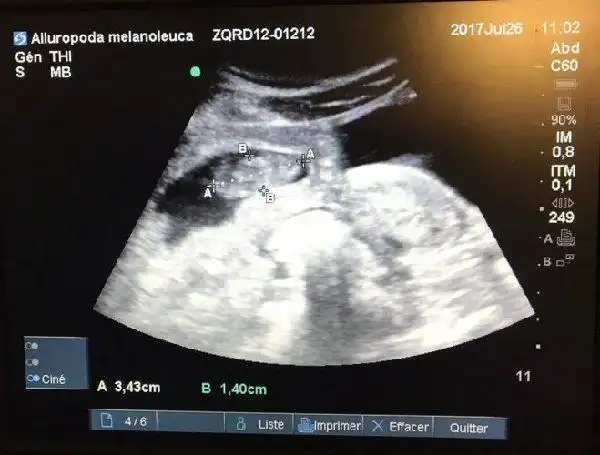

7月26日做的b超检查证实欢欢怀孕了,胚胎长3.4厘米.